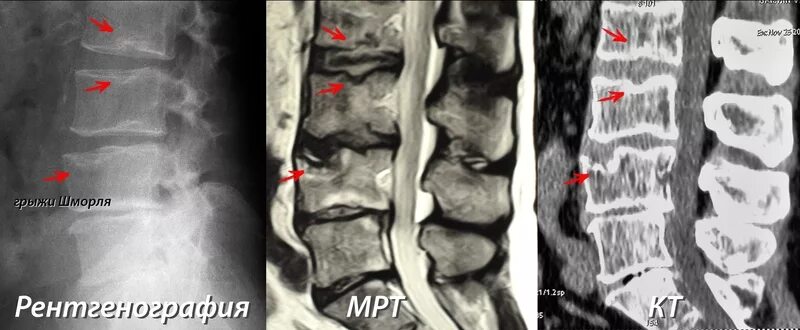

Протрузии шморля